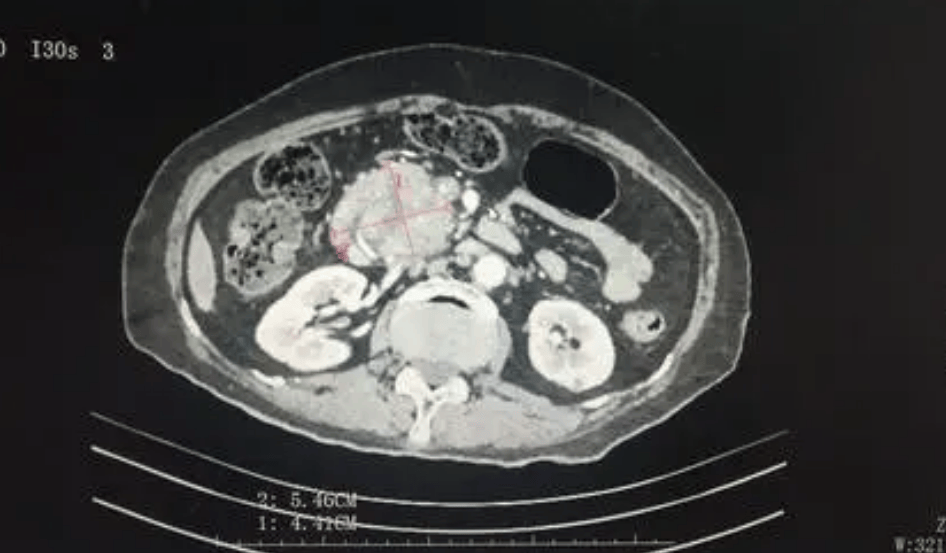

去年4月,本來只是因為一點小咳嗽,去醫院做了個常規的CT平掃,沒想到這一掃,黃女士竟然被AI識別成了疑似早期胰腺癌。

而醫院之所以想到要用AI,是因為她的CT影像被納入了阿里達摩院牽頭的“平掃CT+AI”癌症早篩項目。

返回醫院複查後,AI的判斷果然是對的:胰尾部真的有腫塊!

在使用對比劑進行增強掃描後,確定其大小為25×31mm。這大約是一顆中等大小的葡萄那麼大。

正是因為發現得早,並很快進行了手術,黃女士才從胰腺癌這種全球生存率最低的惡性腫瘤之一的魔爪下倖存了下來。